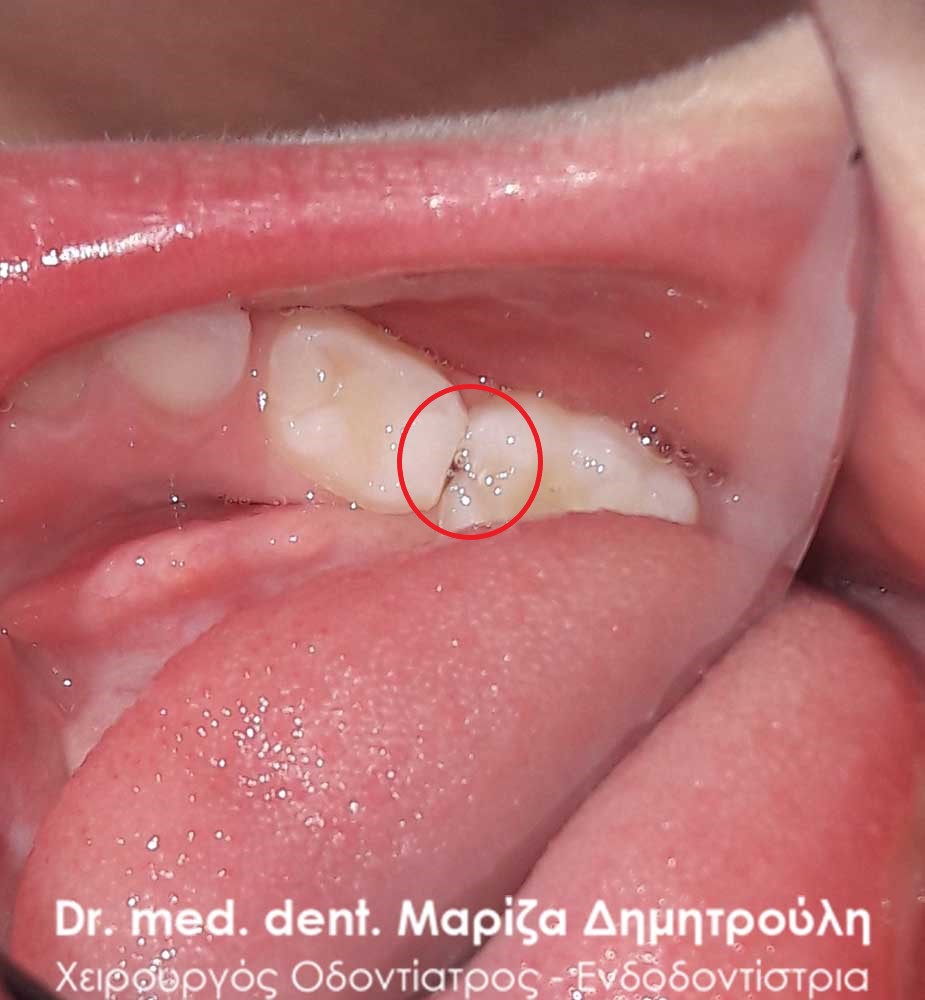

Dental filling of primary tooth

BEFORE